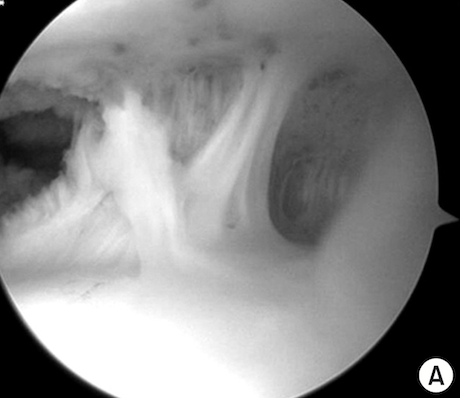

Advanced Imaging

The Extremities